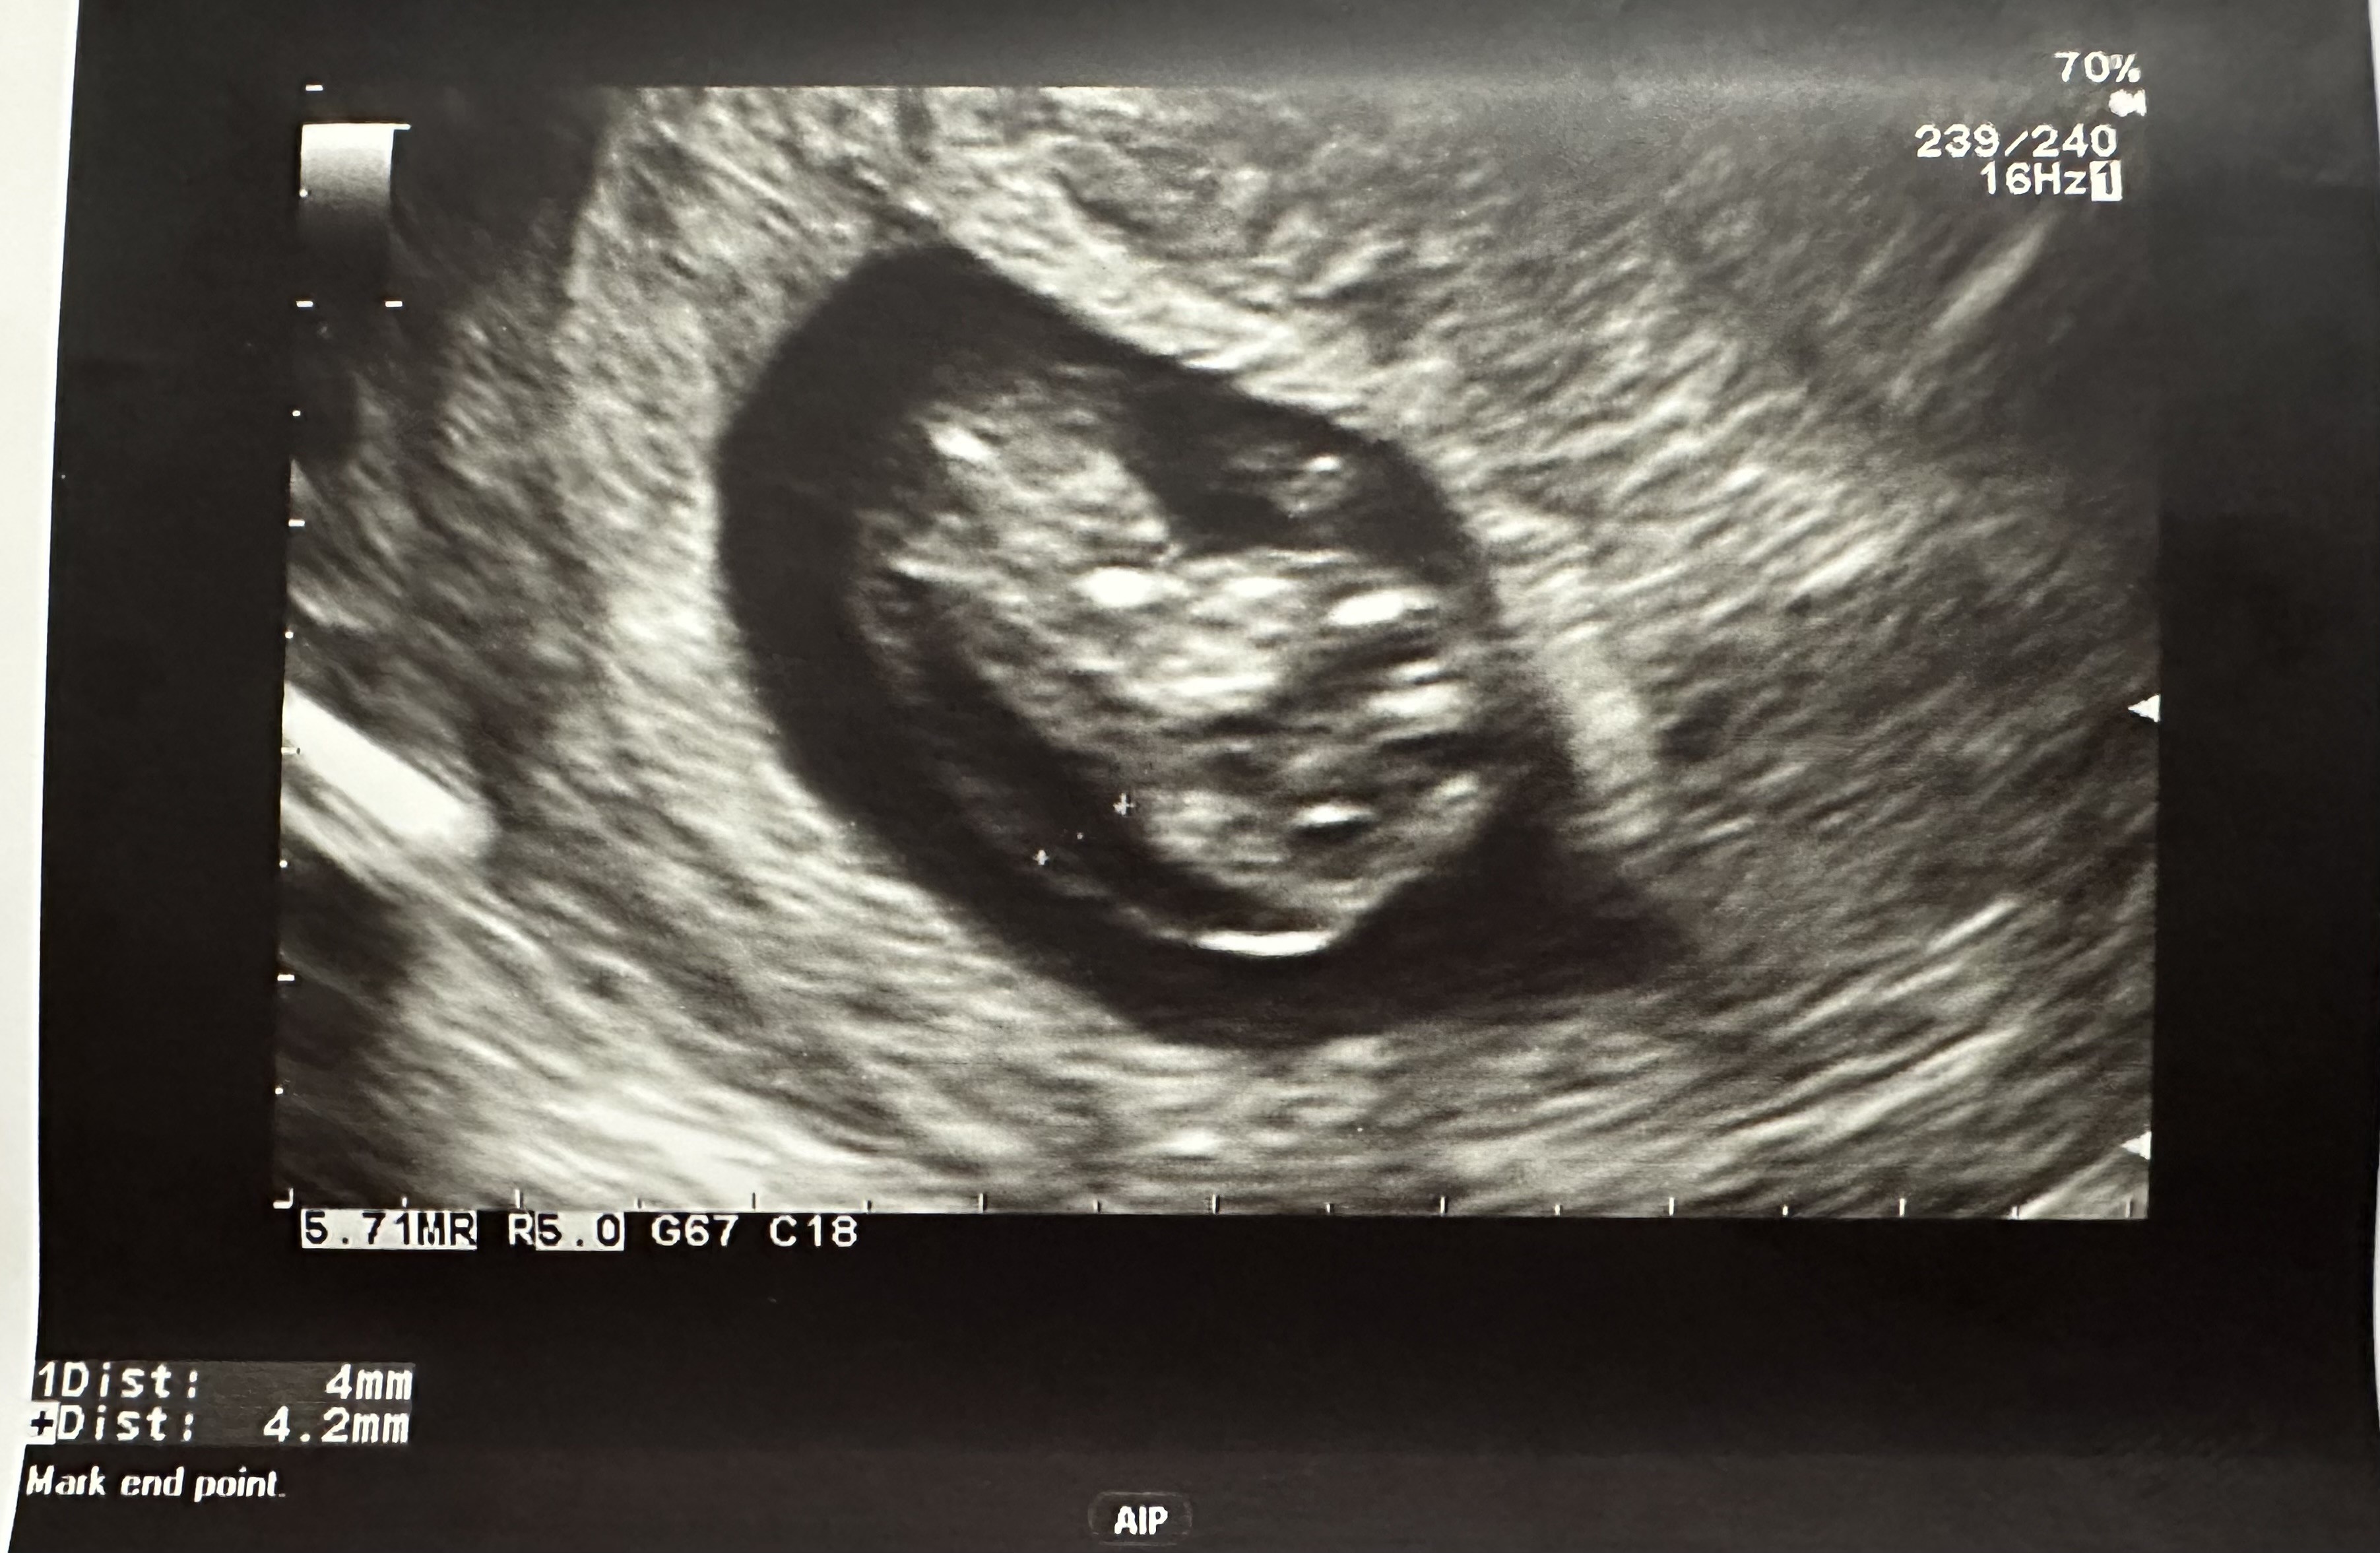

Hej! Dziś po wizycie od ginekologa wyszłam przestraszona z gabinetu. Pani Doktor oczywiście mówiła, że nie mam się czym przejmować, jednak dała mi skierowanie na NFZ na badanie prenatalne. Oznajmiła, że zarodek ma cechy cystic hygroma (przezierność karkowa). Oczywiście po wyjściu z gabinetu troszkę się naczytałam na ten temat… Jestem w 10 + 4 tygodniu ciąży. A fałda karkowa wydaje mi się naprawdę duża. Choć przyznam szczerze - nie za bardzo wiem jak odczytywać wyniki. Dziecko ma 34 mm. Czy któraś z Was była w podobnej sytuacji? I okazało się, że jest wszystko dobrze?

• IMG_4526.jpeg

IMG_4526.jpeg

997,7 KB · Wyświetleń: 583